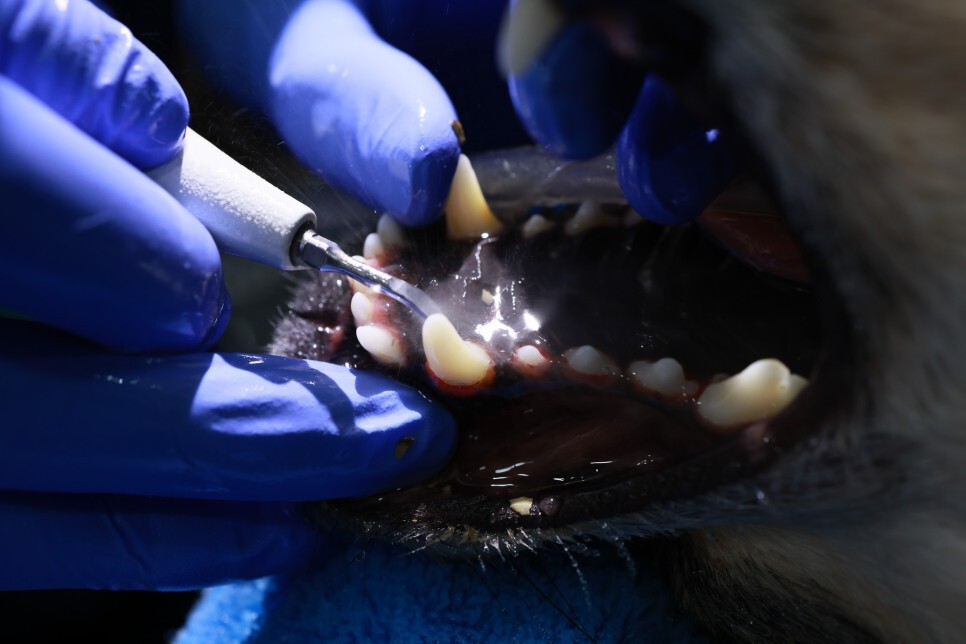

본격적으로 치석제거 시작

와 묵은 때가 씻겨 나오는데

와 내속이 다 시원해짐

치아에서 무슨 검은 가루가 나온다며

뭐 먹였나고??

난들?? 아리??

사료와 간식밖에 없는데

그런데 김하원 갑자기 혈압이 떨어지면서

호흡을 안 함..

자가로 호흡을 안 해서 수동으로 호흡을 시켜줌..

애가 컨디션이 안 좋았나..

이래도 되나 싶을 정도로 꼼꼼하게 해주심 ㅋㅋ

아이들은 스케일링 한 번 받으려면

전신마취가 들어가서

한 번 할 때 아주 꼼꼼하고

완벽하게 해야 하는